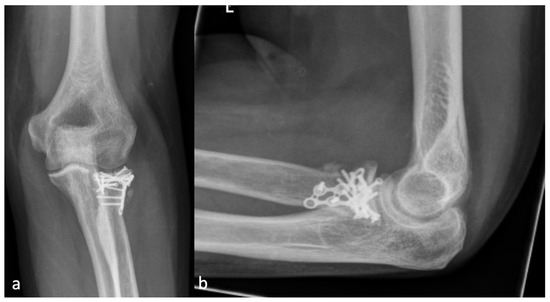

Figure 3.

(a) shows the AP and (b) shows the lateral X-ray with an anterior HO (23.4 mm) which is larger than the diameter of the radial head (19.2 mm) and represents an HO 2a.